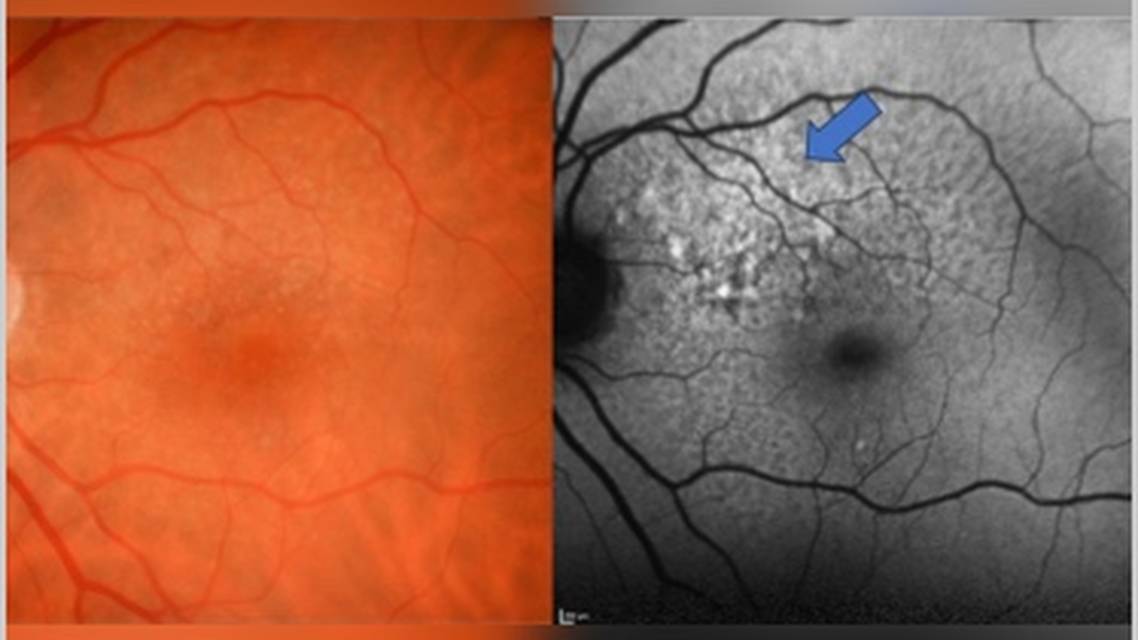

From 2020 to 2023, while treatment for GA did not exist, the patient was educated regarding the presence of her quickly progressive GA and the possibility of treatment in the near future. When intravitreal complement inhibition was FDA approved in 2023, the patient was sent back to me, this time for me to see her at our retina specialty clinic, Charles Retina Institute. This visit was specifically made to discuss initiation of treatment to slow down her GA, and the patient was well educated and prepared to have the conversation. Being familiar with JT’s case, knowing her GA had progressed quickly in the last 3 years, and observing high-risk characteristics such as RPD and hyperautofluorescence surrounding her GA on fundus autofluorescence (FAF) (Figure 3), I believed she was a strong candidate for complement inhibition. We discussed pros and cons of treatment including the increased risk to develop macular neovascularization (MNV). The patient elected to pursue treatment, and she received her first injection of complement inhibition in May 2023.